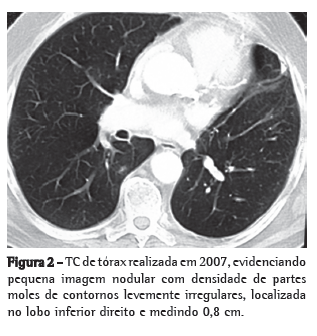

Relato de casoPaciente masculino de 71 anos de idade, com antecedente de lobectomia superior esquerda com ressecção do pericárdio por invasão local e linfadenectomia mediastinal há cinco anos (Figura 1). Estadiamento patológico IIB (T3N0M0). No seguimento com exame de imagem, achado de lesão pulmonar contralateral-0,8 cm no segmento superior do lobo inferior direito-não presente nos controles anteriores (Figura 2).